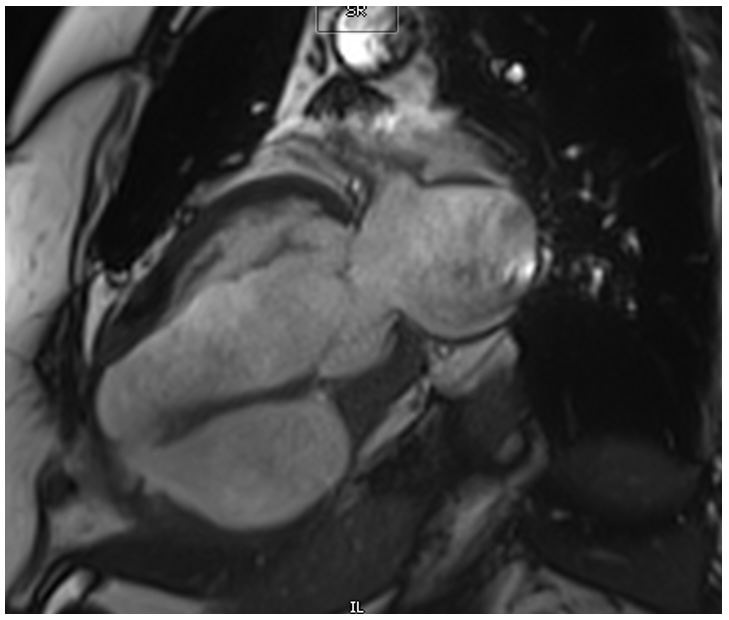

Fig 2. Steady-state free precession (SSFP): Two-chamber view showing communication between the ventricular cavity and the pseudoaneurysmal sac.